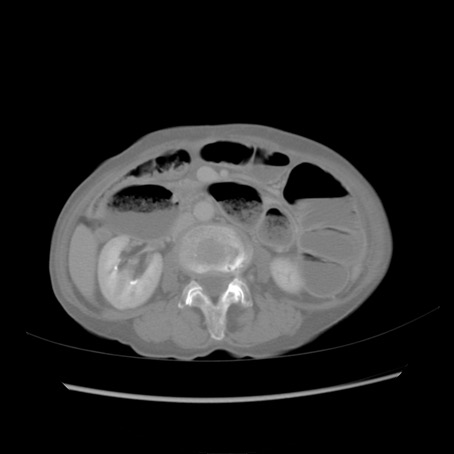

症例25(横断像)

【症例】80歳代女性

【主訴】胸のつかえ感

【現病歴】約9時間前に食後から胸のつかえた感じあり、嘔吐あり、来院。

【既往歴】胃癌(全摘)、胆摘、虫垂炎

【身体所見】心窩部に圧痛あり、反跳痛なし。

【データ】WBC 5700、CRP 0.05